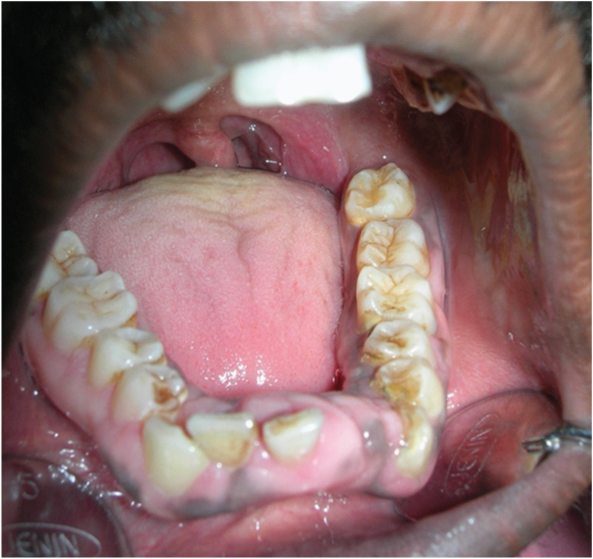

[Table/Fig-3] showing the normal morphology of crowns of the maxillary teeth. [Table/Fig-4] showing the normal morphology of crowns of the mandibular teeth. Full mouth intraoral periapical radiograph revealed complete root resorption in relation to 11, 12, 41 and 42; cervical resorption in 15, 33, 34 and 43, 44; apical resorption in 16, 24, 25 and 26. Resorption in both apical and cervical region was noticed in relation to 35, 36 and 46. Panoramic radiographs showed multiple ill defined radiolucent areas in apical third and cervical region of all teeth in varying degree. Lateral view of skull showed no evidence of any skull changes. In [Table/Fig-5] intraoral periapical radiograph showing complete root resorption in relation to 11 and 12. In [Table/Fig-6] intraoral periapical radiograph showing complete root resorption in relation to 41 and 42. In [Table/Fig-7] intraoral periapical radiograph showing cervical resorbtion in relation to 15 and apical root resorption of mesial and distal roots in relation to 16. Loss of PDL space in 17 can be appreciated.

Showing the normal morphology of crowns of the mandibular teeth